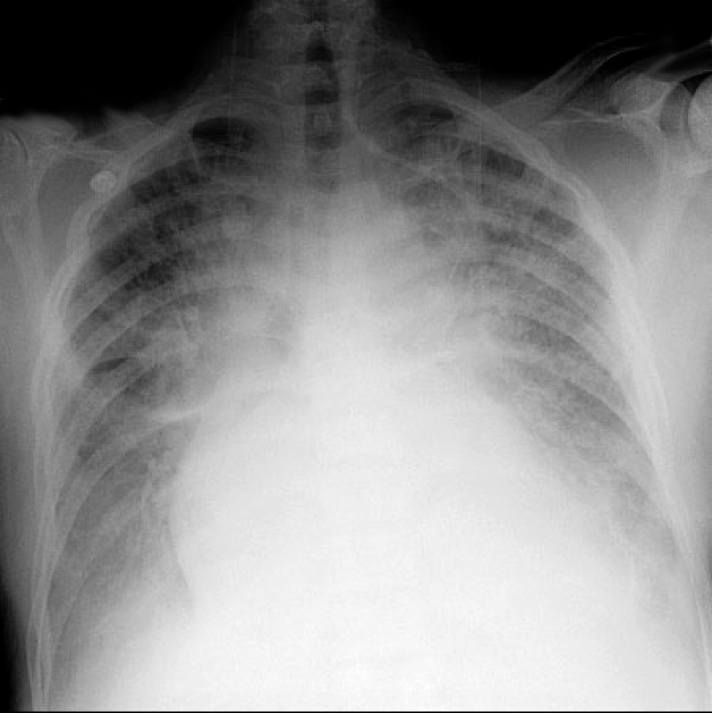

Pulmonary edema

- pulmonary edema